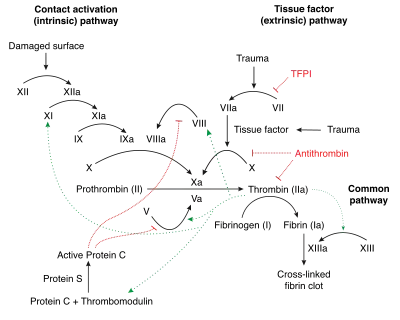

Mechanism of action

In the blood coagulation pathway, thrombin acts to convert factor XI to XIa, VIII to VIIIa, V to Va, fibrinogen to fibrin, and XIII to XIIIa. In the conversion of fibrinogen into fibrin, thrombin catalyzes the cleavage of fibrinopeptides A and B from the respective Aα and Bβ chains of fibrinogen to form fibrin monomers.[13]

Factor XIIIa is a transglutaminase that catalyzes the formation of covalent bonds between lysine and glutamine residues in fibrin. The covalent bonds increase the stability of the fibrin clot. Thrombin interacts with thrombomodulin.[14][15]

As part of its activity in the coagulation cascade, thrombin also promotes platelet activation and aggregation via activation of protease-activated receptors on the cell membrane of the platelet.

Negative feedback

Thrombin bound to thrombomodulin activates protein C, an inhibitor of the coagulation cascade. The activation of protein C is greatly enhanced following the binding of thrombin to thrombomodulin, an integral membrane protein expressed by endothelial cells. Activated protein C inactivates factors Va and VIIIa. Binding of activated protein C to protein S leads to a modest increase in its activity. Thrombin is also inactivated by antithrombin, a serine protease inhibitor.